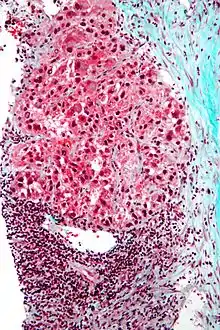

Macroscopically, liver cancer appears as a nodular or infiltrative tumor. The nodular type may be solitary (large mass) or multiple (when developed as a complication of cirrhosis). Tumor nodules are round to oval, gray or green (if the tumor produces bile), well circumscribed but not encapsulated. The diffuse type is poorly circumscribed and infiltrates the portal veins, or the hepatic veins (rarely).[17]

Microscopically, the four architectural and cytological types (patterns) of hepatocellular carcinoma are: fibrolamellar, pseudoglandular (adenoid), pleomorphic (giant cell), and clear cell. In well-differentiated forms, tumor cells resemble hepatocytes, form trabeculae, cords, and nests, and may contain bile pigment in the cytoplasm. In poorly differentiated forms, malignant epithelial cells are discohesive, pleomorphic, anaplastic, and giant. The tumor has a scant stroma and central necrosis because of the poor vascularization.[41] A fifth form – lymphoepithelioma like hepatocellular carcinoma – has also been described.[42][43]